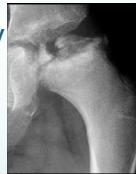

Physical Examination Findings:

- Overweight body habitus

- Hypogonadism signs

- Hip positioning:

- Externally rotated hip at rest

- Loss of internal rotation

- Obligatory external rotation on hip flexion

Clinical examination findings:

(Source: Apley’s System of Orthopedics and Fractures)

Physical examination demonstration: